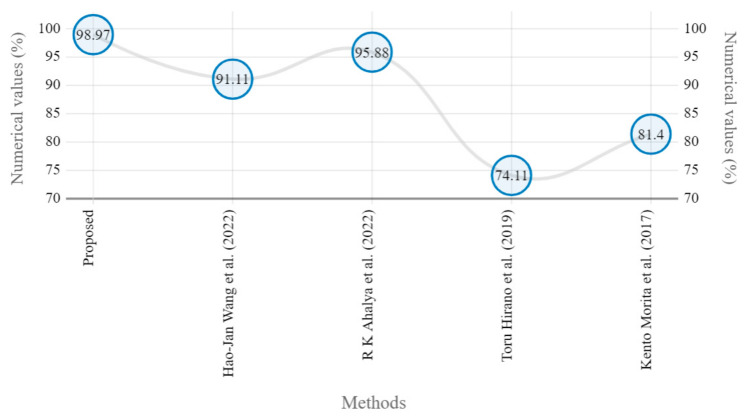

Sample images of the marginal joint space narrowing region of interest can be seen in Figure 5. The IoU (Intersection of Union) metrics were used to evaluate our region of interest detection system. This metric was the size of the intersection between the area of the actual bounding box and the area of the predicted bounding box divided by the size of the area of both boxes added together. When the IoU was 0.70, the narrow marginal joint space was found in 99.72% of the knee joints using our presented model. Additionally, Figure 6 depicts the ROC curve for marginal joint space narrow detection. The results of the presented marginal joint space narrow detection model obtained a sensitivity rate of 98.67%, a Dice score of 98.58%, a precision rate of 98.46%, a specificity rate of 98.50%, a false positive rate of 0.0100, a false negative rate of 0.0197, and an overall accuracy rate of 98.97%, as shown in Table 6, and the graphical illustration of Table 6 values is depicted in Figure 7. Table 7 demonstrates the metric performance outcomes of the proposed ResNet101 and VGG16 model to classify the RA. From Table 7, the outcome of the VGG16 outperforms the well-pre-trained ResNet101 model in classifying RA.

The presented model achieved 99.10% accuracy on the whole test set. The confusion matrix of the presented method is shown in Figure 8, and its performance is compared in detail to that of current methods in Table 5. In Figure 8, we examine the training and learning procedure as a whole to assess the planned activity’s success. Table 6 demonstrates the highest accuracy rate for classifying CBD grades zero–three–four knee joints. The knee joints with a CBD grade of one or two are the toughest to categorize. As can be seen in Figure 8, there is only a marginal amount of room for error when classifying knee joints as CBD Grades zero, three, or four. Knee joints that are classified as CBD Grades one or two have a small number of marginal misclassifications. In several circumstances, the proposed approach incorrectly estimated CBD Grade two as Grade one and vice versa. Joint space narrowing and bony spur development are significantly different in CBD Grade four knee joints. However, CBD-grade one knee joints show little change in JSN or osteophyte growth compared with the other classes. Types of knee RA and their intensity levels are shown in Figure 5. Table 8 and Figure 9 illustrate the JSN accuracy of the proposed and other state-of-the-art methods comparison.

Table 8: JSN outcomes of proposed and state-of-the-art methods.

| Prediction of Marginal JSN Accuracy | ||||

|---|---|---|---|---|

| Models | Sensitivity (%) | Specificity | Precision | Accuracy (%) |

| Proposed model | 98.3 | 97.98 | 98.46 | 98.97 |

| Hao-Jan Wang et al. (2022) [ref. 25] | 90.81 | 89.98 | 91.05 | 91.11 |

| R K Ahalya et al. (2022) [ref. 5] | 94.34 | 94.12 | 95.21 | 95.88 |

| Toru Hirano et al. (2019) [ref. 22] | 73.29 | 73.11 | 73.98 | 74.11 |

| Kento Morita et al. (2017) [ref. 24] | 80.9 | 79.98 | 80.97 | 81.4 |

In this study, we developed a deep learning model to automatically grade the severity of knee RA using a consensus-based approach. We compared the proposed work to prior strategies and found that it outperformed the competition. At the elementary level, notably in Grade one and Grade two, we found that our method differed from that of the medical professionals. We evaluated the presented work by comparing its results with similar existing studies. Compared with previously existing models, the presented work (a knee joint space narrowing diagnosis and class label) fares very well. It takes about 7 h of training to reach 0.6 k iterations. The outcomes of the presented methodology are shown in Table 9, which includes the outcomes of each CBD grade individually. Multiple metrics were employed to estimate the model’s performance, as indicated in Table 10. Figure 10 and Figure 11 depict the ROI curve for RA severity classification for both knees.

Figure 12 shows that the presented system outperformed other methods in terms of sensitivity (Se), specificity (Sp), precision (Pr), accuracy (Acc), and dice score (Ds), demonstrating deep learning’s capability. Figure 13 depicts the CBD grade outcome doughnut chart. In this research, the presented model increased overall ROI detection accuracy by up to 0.5 percent and improved classification accuracy by up to 1.18 percent. The proposed model is more dependable as a result of the detailed knee JSN characteristics. The improvement was satisfactory, and we agree with the observation that the AP view has a significant portion of the information necessary to assess the severity of knee RA with the CBD grading system. The CBD score is often examined using the AP view alone. Table 6 presents a comparison of the output of the proposed methodology with that of other methods that are currently in use. R K Ahalya et al. (2022) obtained Se of 0.9491, Sp of 0.9408 Pr of 0.9213, Acc of 0.9551 and Ds 0.8991; Uma Ramasamy et al. (2022) achieved Se of 0.8891, Sp of 0.8982, Pr of 0.8844, Acc of 0.9012, and Ds of 0.8923; Shawli Bardhan et al. (2021) obtained Se of 0.9785, Sp of 0.9561, Pr of 0.9713, Acc of 0.9864, and Ds of 0.9231; Rabbia Mahum et al. (2021) achieved Se 0.9815, Sp of 0.9789, Pr of 0.9896, Acc of 0.9714, and Ds of 0.9795; Kristine et al. (2022) obtained Se of 0.9012, Sp of 0.9101, Pr of 0.8915, Acc of 0.9211, and Ds of 0.9117; Shawli Bardhan et al. (2020) achieved Se of 0.8889, Sp of 0.8541, Pr of 0.8114, Acc of 0.8671, and Ds of 0.8781; and Sujeet More et al. (2022) obtained Se of 0.9622, Sp of 0.9771, Pr of 0.9831, Acc of 0.9685, and Ds of 0.9121. Our active deep CNN model acquired a knee joint identification accuracy of 98.97% and a knee RA severity classification accuracy of 99.10% using the presented methodology. This model also gives superior performance to handmade features. The active deep CNN model that we have presented and the pre-trained domain adaptation models that are employed in our system produce improved prediction accuracy outcomes for the five classes of knee RA that were experimentally determined.